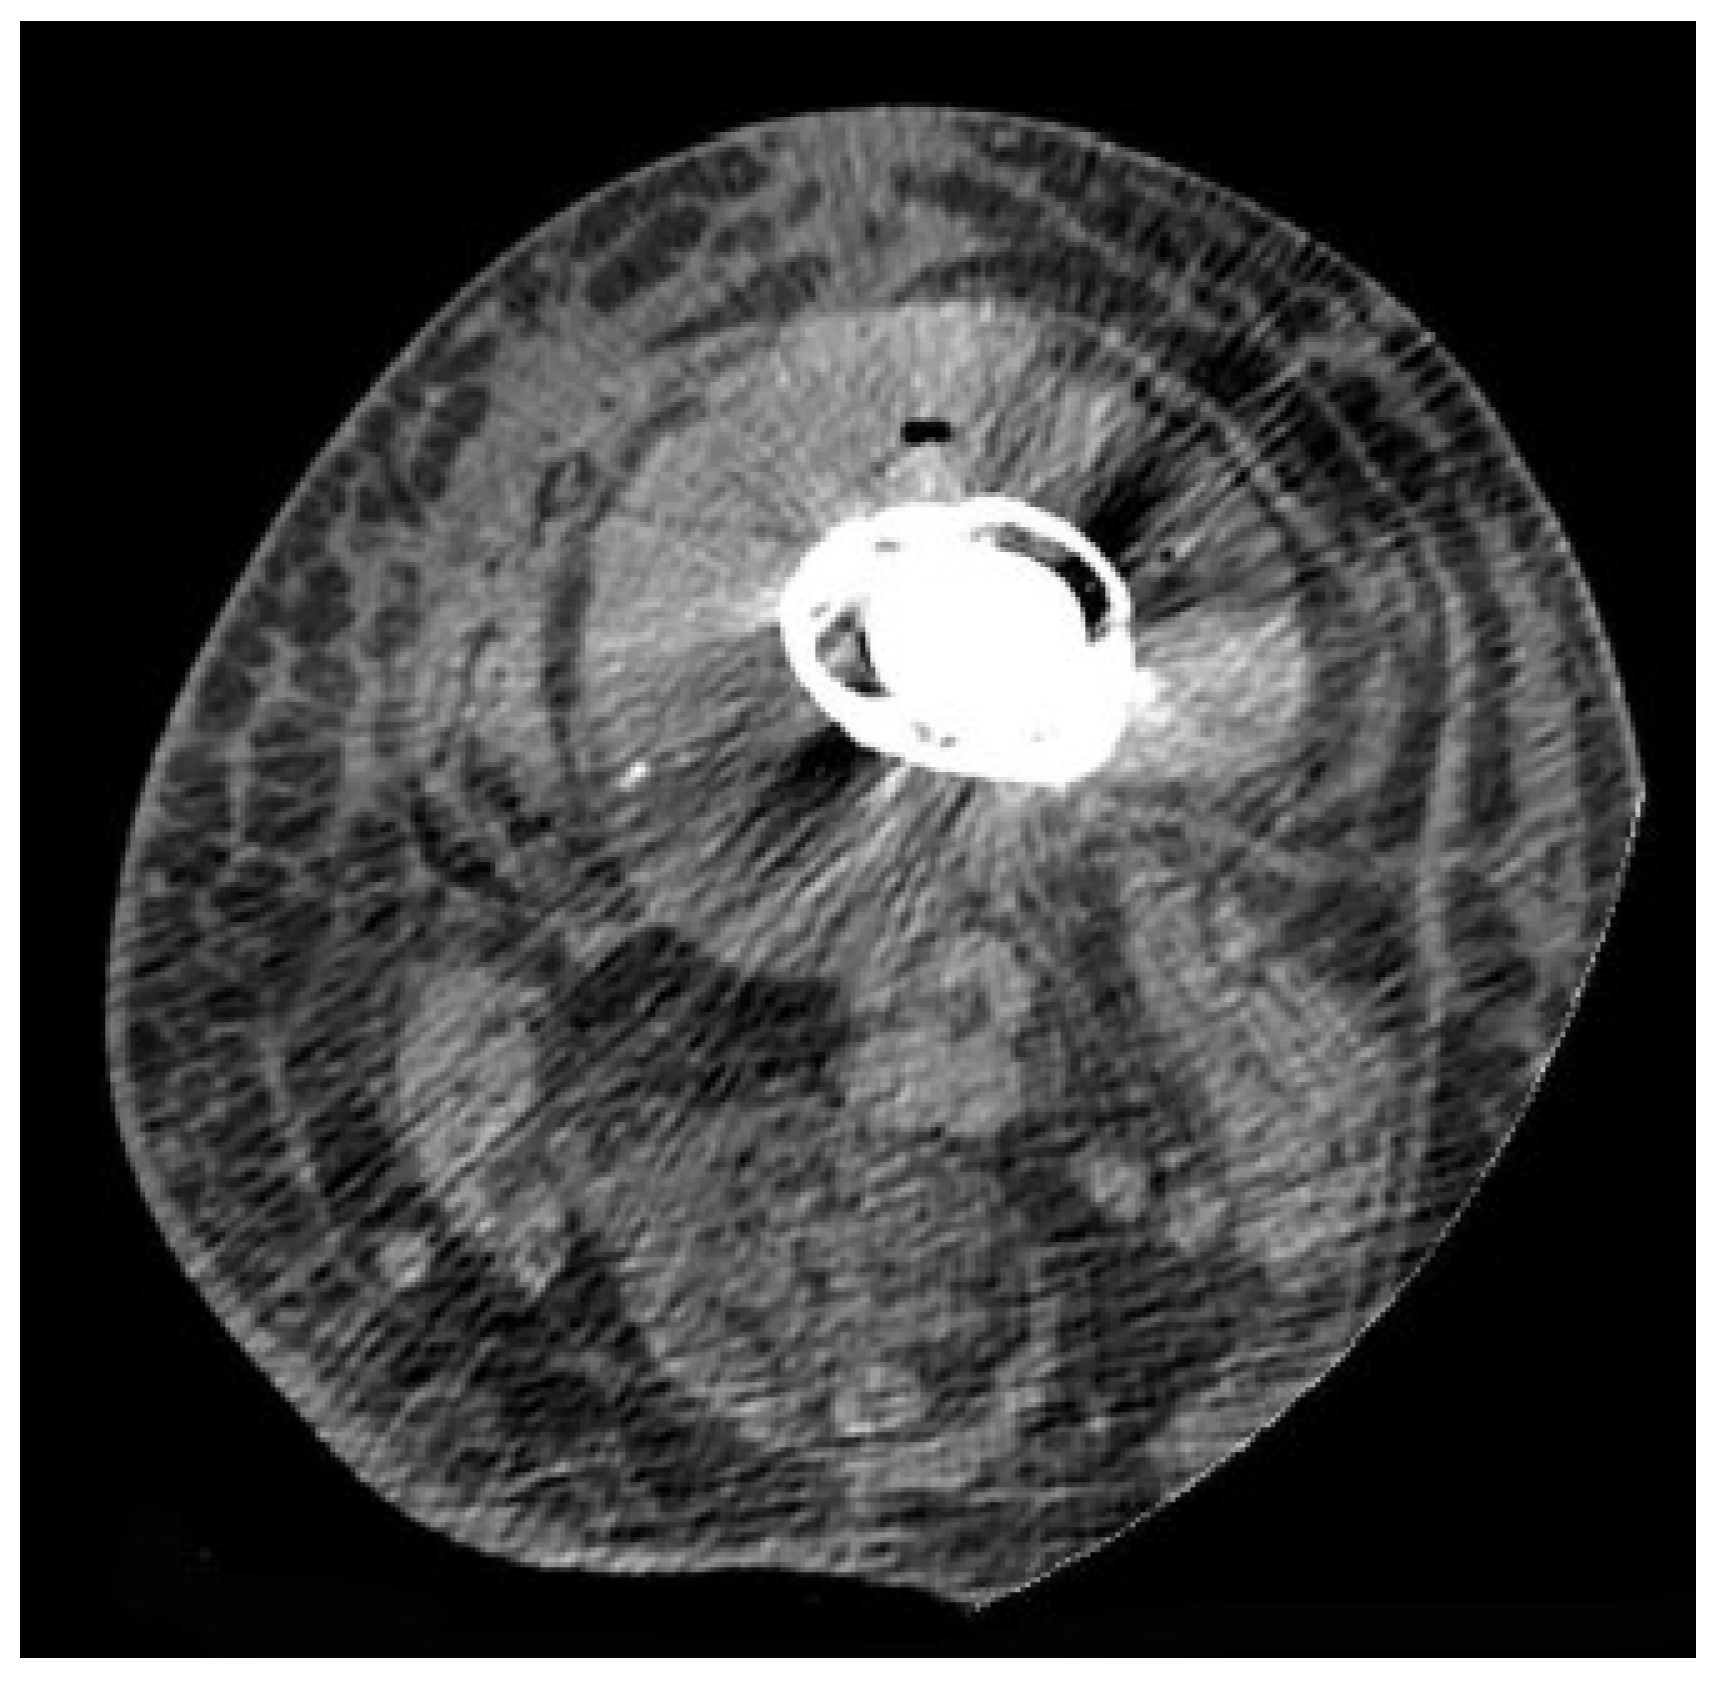

4.3. Computed Tomography

- Miller, T.T. Imaging of hip arthroplasty. Eur. J. Radiol. 2012, 81, 3802–3812. [Google Scholar] [CrossRef]

- Sodhi, N.; Jacofsky, D.J.; Chee, A.; Mont, M.A. Benefits of CT Scanning for the Management of Knee Arthritis and Arthroplasty. J. Knee Surg. 2021, 34, 1296–1303. [Google Scholar] [CrossRef] [PubMed]

- Jacquier, A.; Champsaur, P.; Vidal, V.; Stein, A.; Monnet, O.; Drancourt, M.; Argenson, J.N.; Raoult, D.; Moulin, G.; Bartoli, J.M. [CT evaluation of total HIP prosthesis infection]. J. Radiol. 2004, 85, 2005–2012. [Google Scholar] [CrossRef] [PubMed]

- Cyteval, C.; Hamm, V.; Sarrabère, M.P.; Lopez, F.M.; Maury, P.; Taourel, P. Painful infection at the site of hip prosthesis: CT imaging. Radiology 2002, 224, 477–483. [Google Scholar] [CrossRef]

- Różyło-Kalinowska, I. Computed Tomography (CT). Imaging Temporomandibular Jt. 2019, 115–123. [Google Scholar] [CrossRef]

- Schmidt, C.W. CT scans: Balancing health risks and medical benefits. Environ. Health Perspect. 2012, 120, 119–121. [Google Scholar] [CrossRef]

- Isern-Kebschull, J.; Tomas, X.; García-Díez, A.I.; Morata, L.; Ríos, J.; Soriano, A. Accuracy of computed tomography–guided joint aspiration and computed tomography findings for prediction of infected hip prosthesis. J. Arthroplast. 2019, 34, 1776–1782. [Google Scholar] [CrossRef] [PubMed]

- Romanò, C.L.; Petrosillo, N.; Argento, G.; Sconfienza, L.M.; Treglia, G.; Alavi, A.; Glaudemans, A.W.; Gheysens, O.; Maes, A.; Lauri, C. The role of imaging techniques to define a peri-prosthetic hip and knee joint infection: Multidisciplinary consensus statements. J. Clin. Med. 2020, 9, 2548. [Google Scholar] [CrossRef] [PubMed]